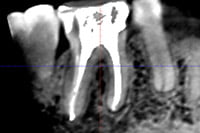

また、レントゲン写真だけでは、歯茎の腫れの原因になっている病巣が見えない事があります。しかし、CTを使えばレントゲン写真では見えなかったむし歯や膿などの病巣をはっきり確認できるケースがあり、原因となっている歯の特定、歯の破折の有無、歯の周りの骨の吸収の有無、歯の神経が通っている根管の形態など、CT画像からはレントゲン画像からは得られにくい様々な情報を得ることができます。もはや、医科と同様、歯科領域でもCT無しでの診断はあり得ない時代になっています。

それは、CT画像を用いた根管の通り道の分析と歯科用顕微鏡を使った根管治療です。

再根管治療では、根管に潜むバイ菌を殺菌・消毒することが特に重要になりますが、根管は三次元的に湾曲していたり、複雑に枝分かれしていたりしていて、実際に根管を殺菌・消毒することは困難を極めることも多いです。再根管治療前に、根管の状態を事前に把握できれば、治療時に注意しなければいけないポイントがわかり、それを治療に反映できるのですが、レントゲン画像では二次元的な画像しか得られないので、根管の走行の把握が足りずに治療の一部が経験や勘の治療になってしまいます。CT画像では根管の三次元的な画像が得られ、レントゲン画像より詳しく根管の状態を把握でき、根管の湾曲具合や未治療の根管の見落としなど、どこを注意しなければいけないかがわかり、勘の治療をせずにすみます。より根管を確実に殺菌・消毒するためには、根管のCTスキャンが有効なのです。

診断に関しては、歯根破折は肉眼や拡大鏡、レントゲン画像ではわかりづらく、CT画像と歯科用顕微鏡を組み合わせて診断するのが有効です。

一見、レントゲン画像ではわかりづらくても、CT画像だと特有の歯槽骨の吸収画像が見られ、確定ではありませんが歯根破折を予測する事ができます。そして、破折が予想されるところを顕微鏡を使用して強拡大で視認することにより、歯根破折を確定診断することができます。